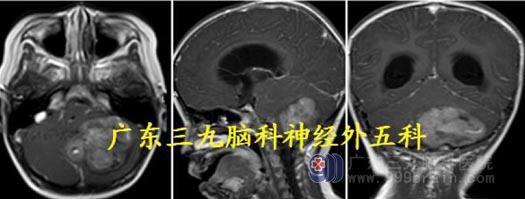

头颅MR:右侧小脑半球占位性病变呈大囊小结节改变,范围约58×42×49mm,边界尚清,增强后病变实性病变呈明显强化,其内间隔示线样轻度强化,囊性部分未见强化。考虑血管母细胞瘤合并幕上梗阻性脑积水、小脑扁桃体下疝;